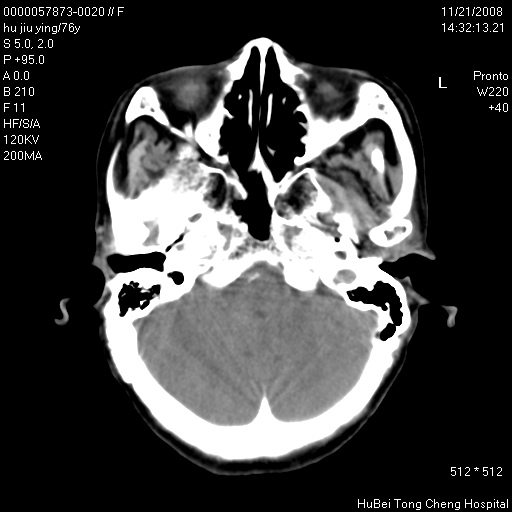

患者 女,76岁。左颈部包块20余天。pe:左侧扁桃体ⅲ度肿大,表面不平,有新生血管,右咽柱红肿,无溃疡。左颈上部包块约3cm×4cm大小,质中等,压痛,边界不清,不能移动。

临床诊断:左侧扁桃体肿瘤?

咽部及颈部ct轴位平扫(层厚、层距均为5mm),图像如下:

左侧咽旁软组织密度肿块影,形态不规则,与周围结构分界欠清,性质待定,建议增强;另双侧上颌窦炎.